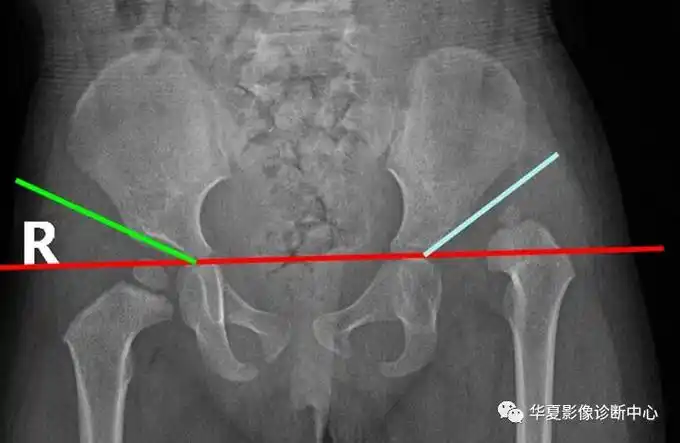

髋关节的x线测量

20张图掌握髋关节x线检查的各种"线与角" - 知乎